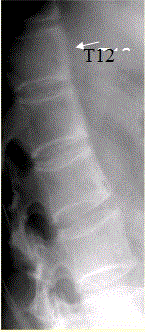

问题 患者男,35岁,外伤后行腰椎CR检查,结果如下图。 观察此张X线片,正确的是

选项 A.所示椎体未见异常 B.T12、L1、L2椎体前缘毛糙 C.L1椎体可疑压缩性骨折 D.所见椎体密度增高 E.所见椎体密度减低 F.建议CT检查,观察椎小关节及骶髂关节 G.建议MRI检查,观察椎体有无异常

答案 BFG